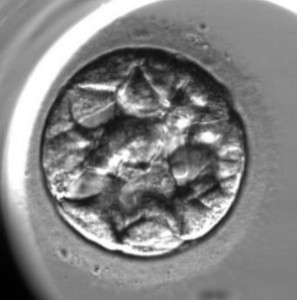

L’enregistrement du développement de l’embryon est le suivant :

Le commencement du compactage de l’embryon

L’apparition d’une cavité dans l’embryon (le commencement d’une blastulation)